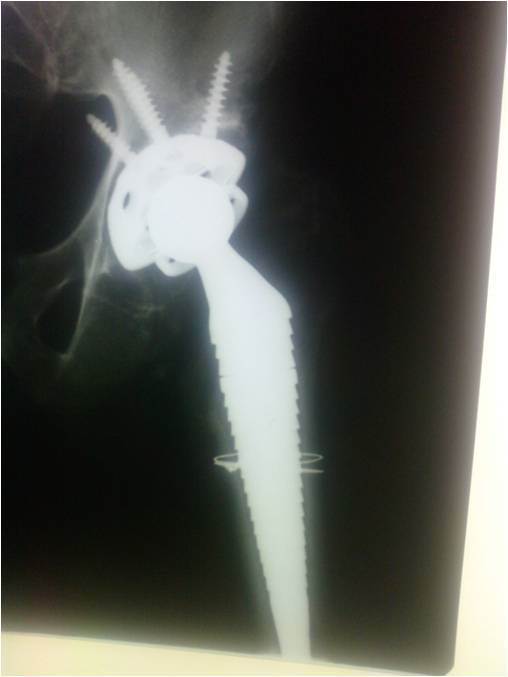

Had 1st & 2nd stage revision with osteotomy & spacer first, then long stem and captive cup